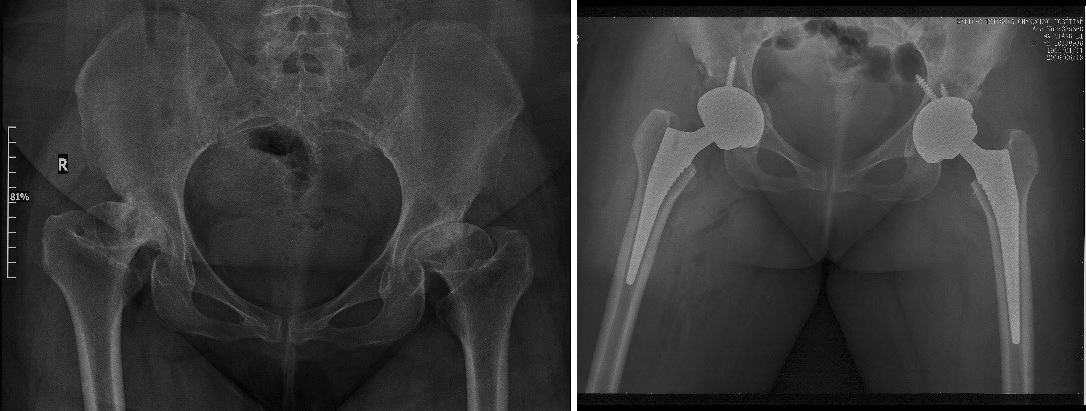

强直性脊柱炎双髋强直

一、人工关节置换 各种晚期骨关节病的关节置换手术治疗是北京清华长庚医院关节外科中心的一大特色,包括股骨头坏死、髋膝骨关节炎、类风湿关节炎、强直性脊柱炎、髋关节发育不良、关节强直、超过80岁的超高龄股骨颈骨折患者的关节置换手术等,我中心在人工关节初次置换及翻修上作了大量工作,置换的难度和手术效果方面已达到国际先进水平,导航下全膝关节置换术:大大提高膝关节置换手术的精确度。

骨科关节外科中心,由骨科副主任、关节外科中心主任蔡谞教授亲自领衔,运动医学专家陈连旭教授辅助,汇集了来自解放军总医院(301医院)、北医三院、积水潭医院、协和医院骨科关节专业的医师,组成国内顶尖的关节诊疗团队。蔡谞教授,原解放军总医院(301医院骨科主任医师,博士研究生导师),国内著名关节外科专家。对关节外科疾病有丰富的诊治经验,尤其专重于人工关节置换和翻修手术以及关节镜下微创手术等关节外科治疗。对股骨头坏死、晚期风湿类风湿性关节炎、先天性髋关节发育不良、骨性关节炎、强直性脊柱炎等骨科常见病和疑难病症的诊治具有丰富的临床经验。许多高难度人工关节置换手术曾无人敢于问津,在我院骨科关节中心已是常态化手术。高难度髋、膝人工关节置换和人工关节翻修手术的临床疗效达到国际先进水平。